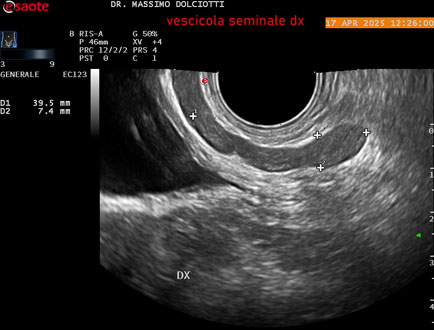

Data inserimento: 01/10/2025

Ecografia del: 17/04/2025

Strumento: Esaote MyLab Eight

Sonda: Convex Multifrequenza 1-8 MHz, Endocavitaria Multifrequenza 3-9 MHz e 3-13 MHz

Età Paziente: M 35 anni

Motivazione dell'esame: disuria.

Commento all'esame: le immagini ed il video documentano la prostata di ecostruttura regolare e morfovolumetria normale con diametro trasversale di 40 mm, diametro anteroposteriore di 21 mm e diametro longitudinale di 43 mm, con volume prostatico calcolato di 18 cc (v.n. < 20 cc), il profilo prostatico è regolare e netto, non si documentano calcificazioni intraghiandolari, la vascolarizzazione della ghiandola è normale. La vescicola seminale destra presenta diametro longitudinale di 44,4 x 7,8 mm, la vescicale seminale sinistra ha diametro longitudinale di 45,3 mm x 7,2 mm.

Conclusioni: prostata normale (normal prostate).